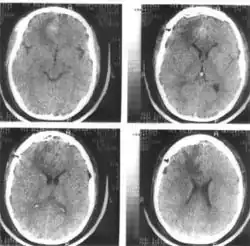

Компьютерная томография головного мозга. Гипертензионная субкортикальная гематома в правой лобной доле

Компьютерная томография головного мозга того же больного через 4 дня после операции — удаления внутримозговой гематомы правой лобной доли